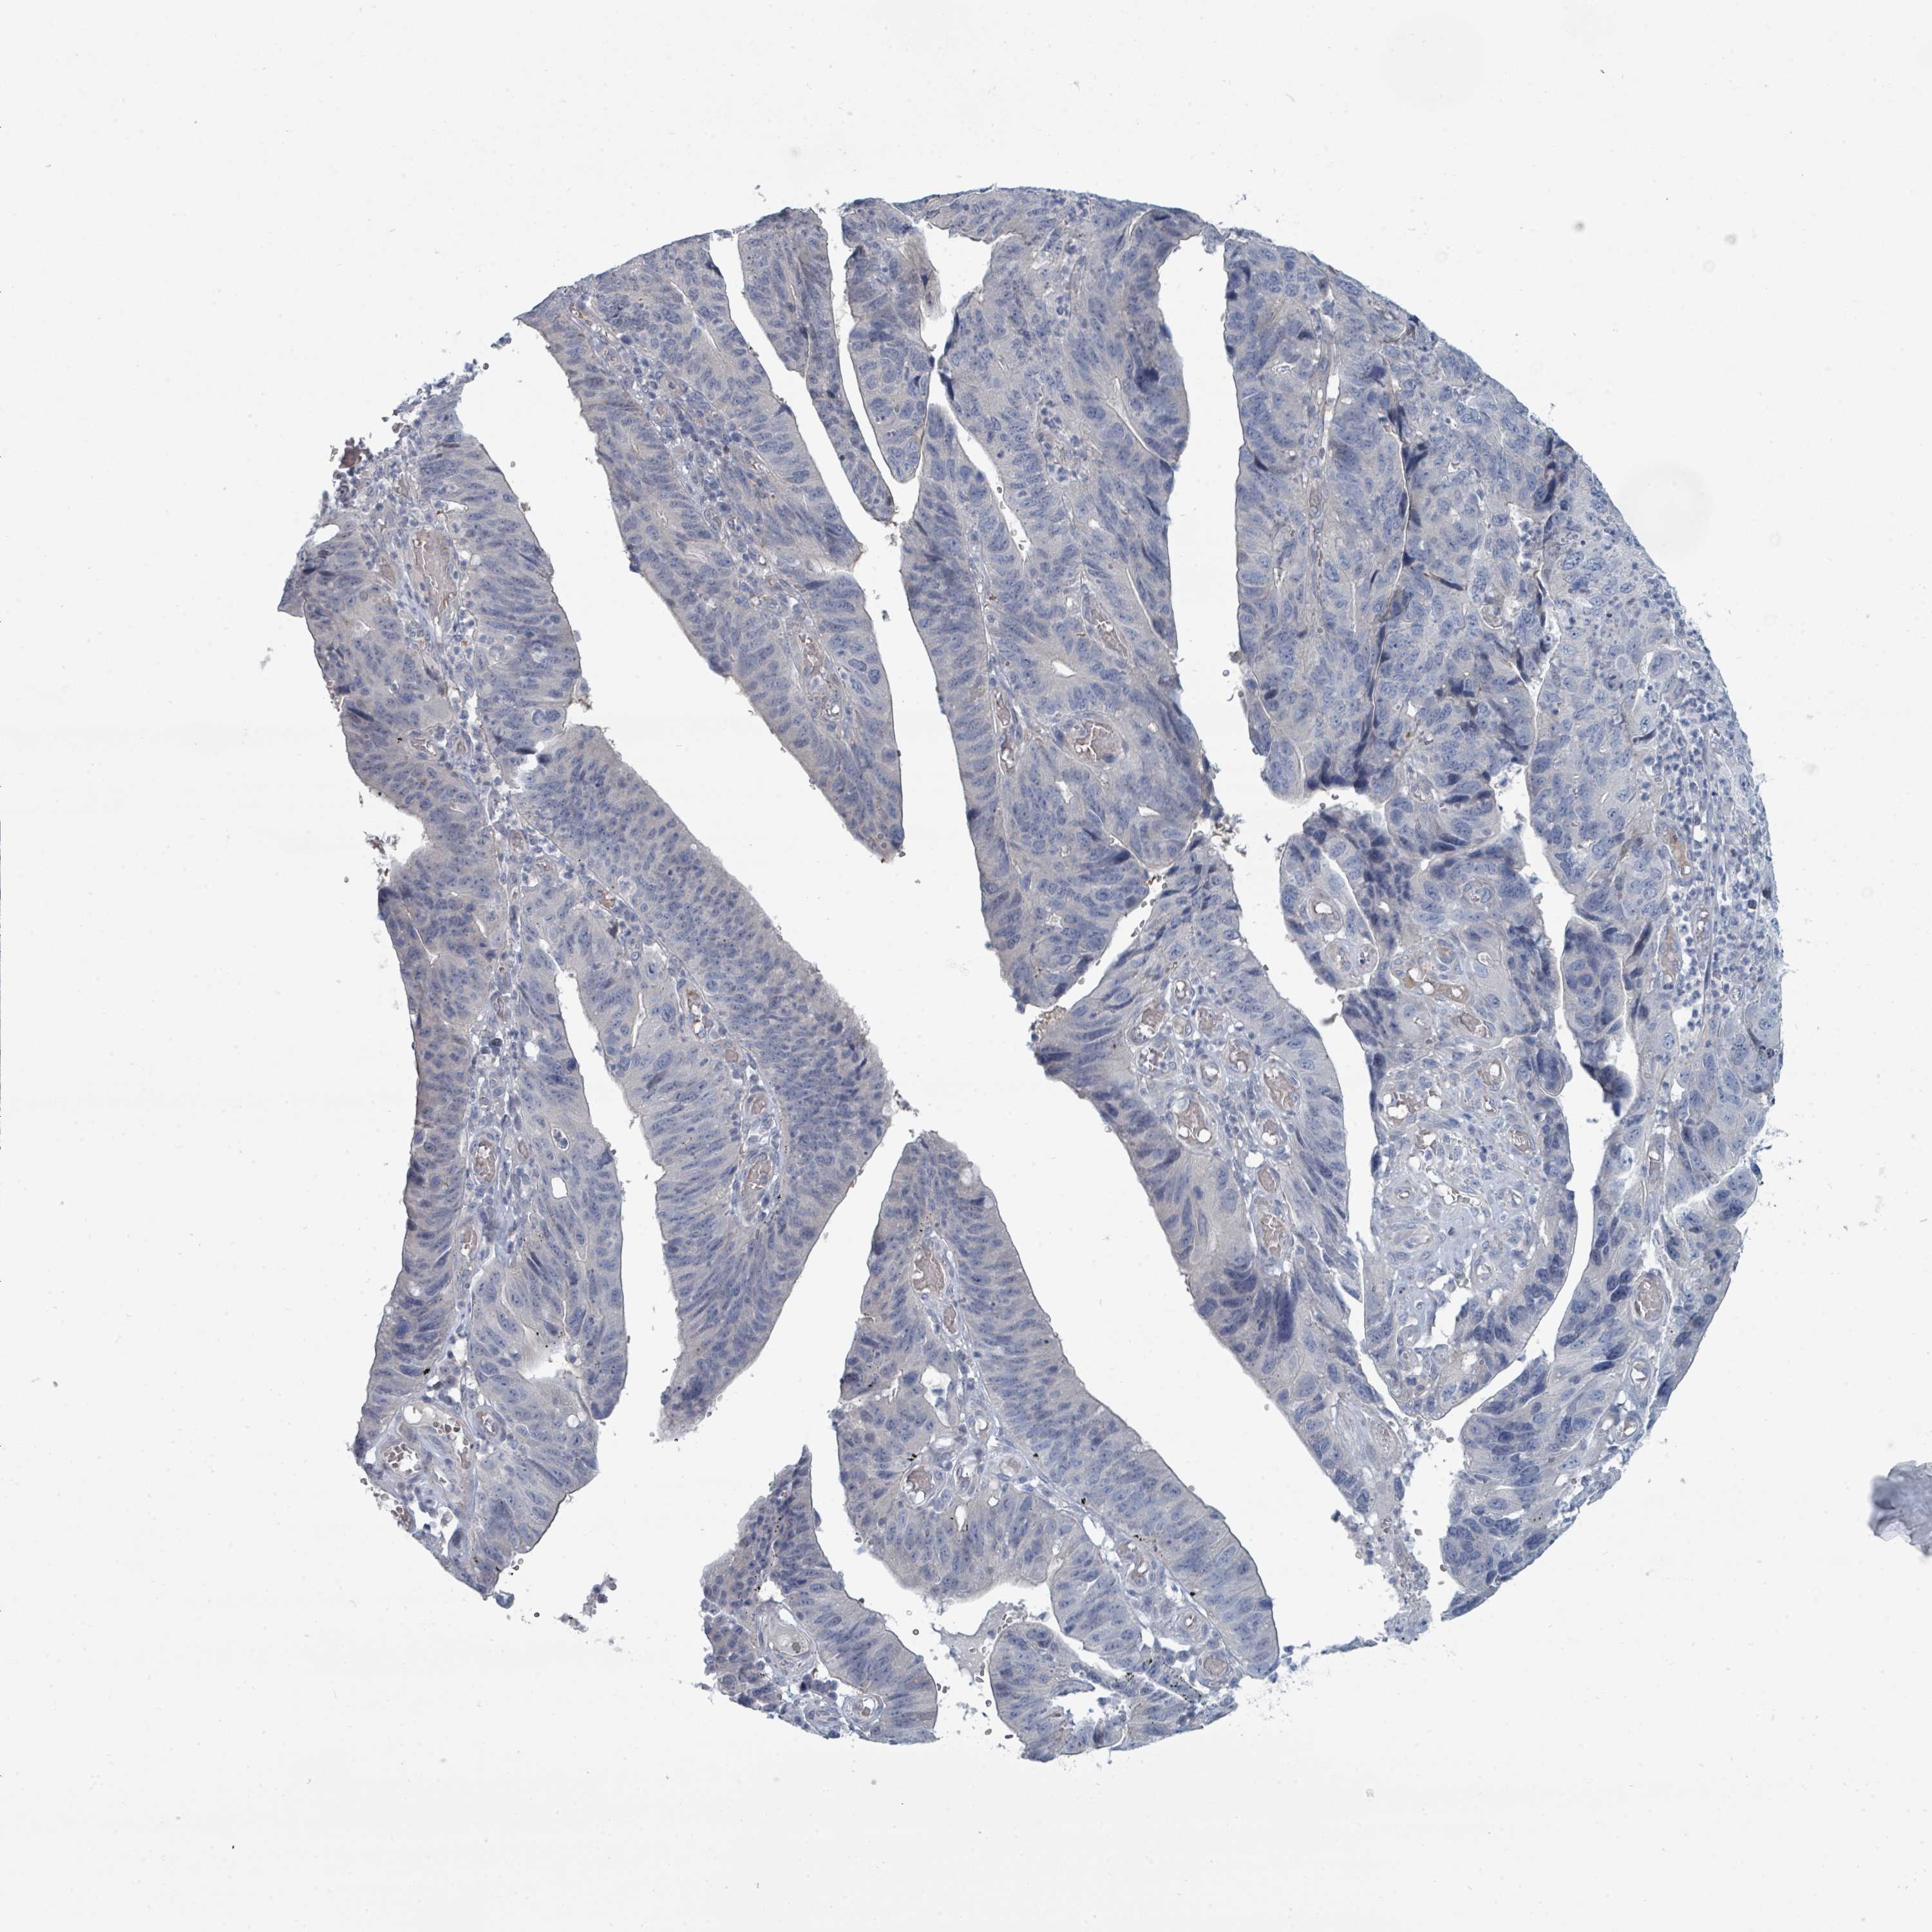

STOMACH CANCER - Protein expressioni

A mouse-over function shows sample information and annotation data. Click on an image to view it in a full screen mode. Samples can be filtered based on level of antibody staining by selecting one or several of the following categories: high, medium, low and not detected. The assay and annotation is described here.

Note that samples used for immunohistochemistry by the Human Protein Atlas do not correspond to samples in the TCGA dataset.

Antibody stainingi

Antibody staining in the annotated cell types in the current human tissue is reported as not detected, low, medium, or high, based on conventional immunohistochemistry profiling in selected tissues. This score is based on the combination of the staining intensity and fraction of stained cells.

Each image is clickable and will lead to virtual microscopy that enables deeper exploration of all samples and also displays staining intensity scores, fraction scores and subcellular localization as well as patient and tissue information for each sample.

Antibody HPA050821

Staining

High

Medium

Low

Not detected

Intensity

Strong

Moderate

Weak

Negative

Quantity

>75%

75%-25%

<25%

None

Location

Nuclear

Cytoplasmic/membranous

Cytoplasmic/membranous,nuclear

Adenocarcinoma, NOS